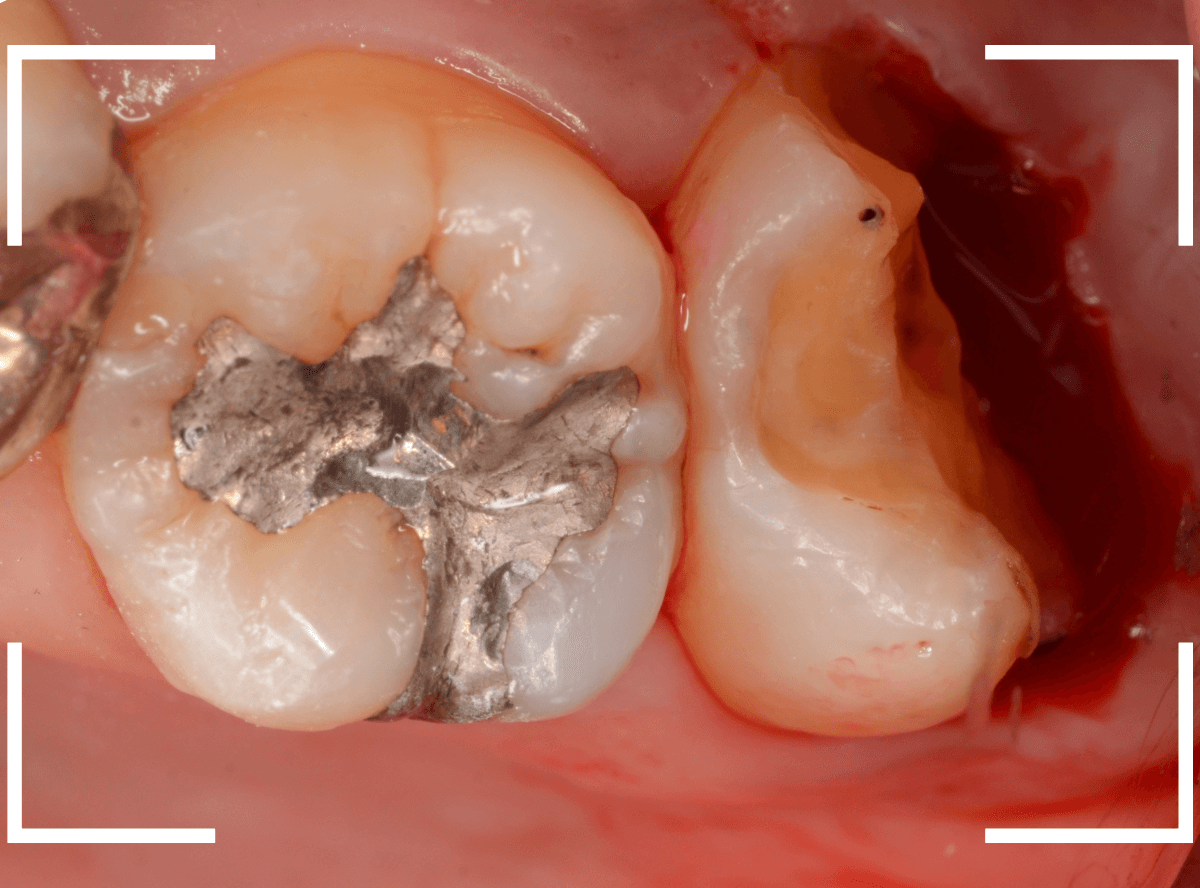

Case.14 インレーの下の歯肉まで広がった虫歯

「下の奥歯が噛むと痛む」という症状で来院された患者さんのケースです。

お口の中の状態を確認すると、奥歯の端に穴が開いているのが見えます。

虫歯が深く、歯肉の下まで浸食していましたので、歯肉を部分切除し、虫歯を全て除去したところで、奇跡的に神経スレスレの状態でとどまっていました。

何とも言えませんが、神経を残せる可能性が出てきました。

虫歯が神経まで達していなくても、治療前から自発痛(何もしなくても痛い)があれば、神経をとらなければいけません。

今回は、そこまでの症状がありませんでしたので、患者さんと相談の上、神経を取らずに残す方法で様子を見る事になりました。